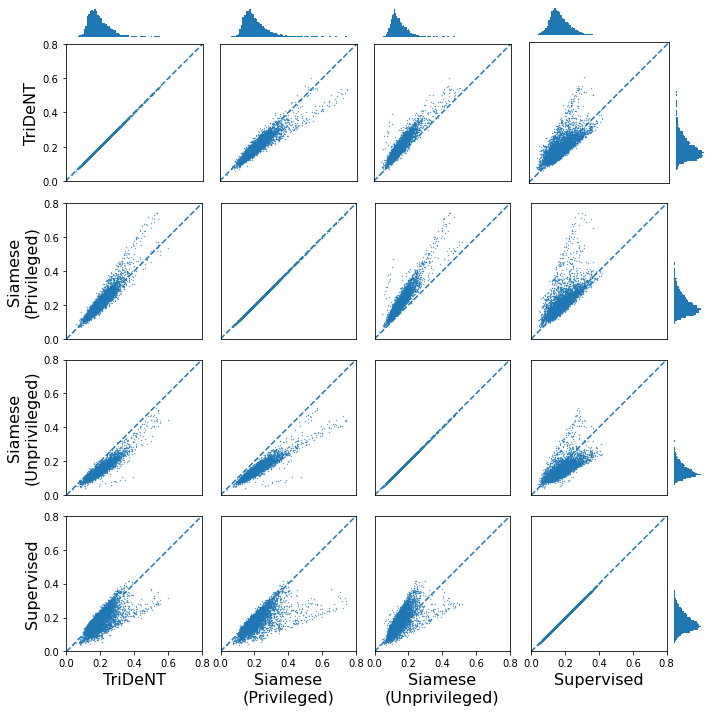

To assess the level of information shared between the transcriptomic results and the representations of the H&E patches, we investigate the cross-correlation between elements of the representations and the gene counts for each matching patch. We calculate the cross-correlation across the validation set between each element in the representations and the count for each gene, and for each gene take the correlation of the corresponding element with the maximum correlation or minimum anti-correlation, whichever has the greater absolute value. This maximum/minimum is chosen because the vast majority of elements will not correlate with any given gene, and the absolute value is taken because the sign of the element is arbitrary, so correlation and anti-correlation are equivalent. We use the absolute value of the correlation for the element selected for each gene, and use these to generate the histograms in Figure 3(a). It is clear that privileged training obtains representations which are far more correlated to the gene counts than unprivileged training, with minimal differences in the correlations between TriDeNT ♆ and Siamese approaches. This implies that the models have learned equivalently informative representations about the coarse-grained features of the genes. Figure 3(c) demonstrates that the correlation strength is significantly greater for TriDeNT ♆ compared to an unprivileged Siamese model, and Figures S3 and S4 show the relationships between the gene correlations of representations from TriDeNT ♆, Siamese methods, and supervised learning. Figures S5 and S6 show the geneset enrichment for each method, demonstrating that TriDeNT ♆ captures more meaninful interrelationships that are more informative about the relationship between tissue morphology and gene expression than unsupervised Siamese models. This is especially important for scientific discovery, as these analyses are used to generate hypotheses for further research. Figure S7 shows UMAP projections of the representation space coloured by genotype and gene, to illustrate that TriDeNT ♆ identifies distinct morphological clusters which are not found by unprivileged Siamese models. Figure 3(a) also shows that the findings are robust to human and mouse datasets, indicating the generality of the method.

To further analyse the learned representations, we produce UMAP projections of the latent space labelled with the tissue types for the NCT tissue type classification task, as shown for CD3CD20 and SMA in Figure 4(a), and for all SegPath stains in Figures S8 and S9. These figures make the reasons for the varying performance of the privileged Siamese model more apparent. For stains with better performing privileged Siamese models, such as SMA, the UMAPs are very similar between Siamese methods and TriDeNT, with well-differentiated tissue type clusters. In those with worse performance, such as ERG, the tissue types are poorly differentiated, often with only adipose and background forming distinct clusters from the other classes. On closer inspection, it is notable in these projections that TriDeNT ♆ produces more well-defined and separated clusters in general than Siamese networks. This is further evidenced in Figure S7, where TriDeNT ♆ is shown to identify clusters with overexpression of a given gene significantly more effectively than an unprivileged Siamese model.